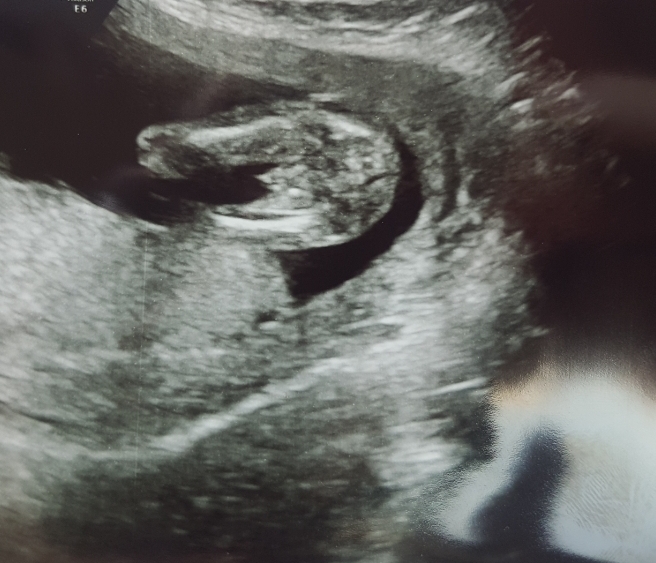

After struggling with fertility for three years our prayer came true and we now have a 16w6 healthy baby.

Truly hoping for a boy which the dr confirmed yesterday, but i am hearing about a lot of incorecly predicted early scans.

Do you agree bellow scan is a definit boy?

Attachment 39758